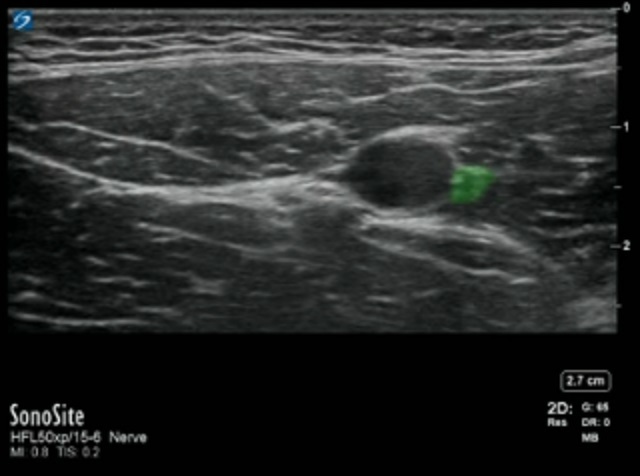

Adductor Saphenous Nerve Image

Highlighted Area: Saphenous Nerve